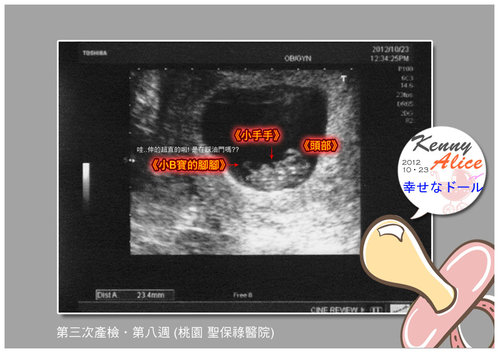

哈哈.....楊醫生 很仔細的與我說明小B寶的現況,還刻意放大小B寶的影像

讓我更仔細的了解....小B寶的狀況...小B寶在動ㄟ...不誇張,我的小B寶真的在動...

我看得到他可愛的小小小手 小小小腳...真的好可愛唷!!

===== 這張小B寶更是清楚,頭頭 小手 小腳腳都相當清楚唷!! =====